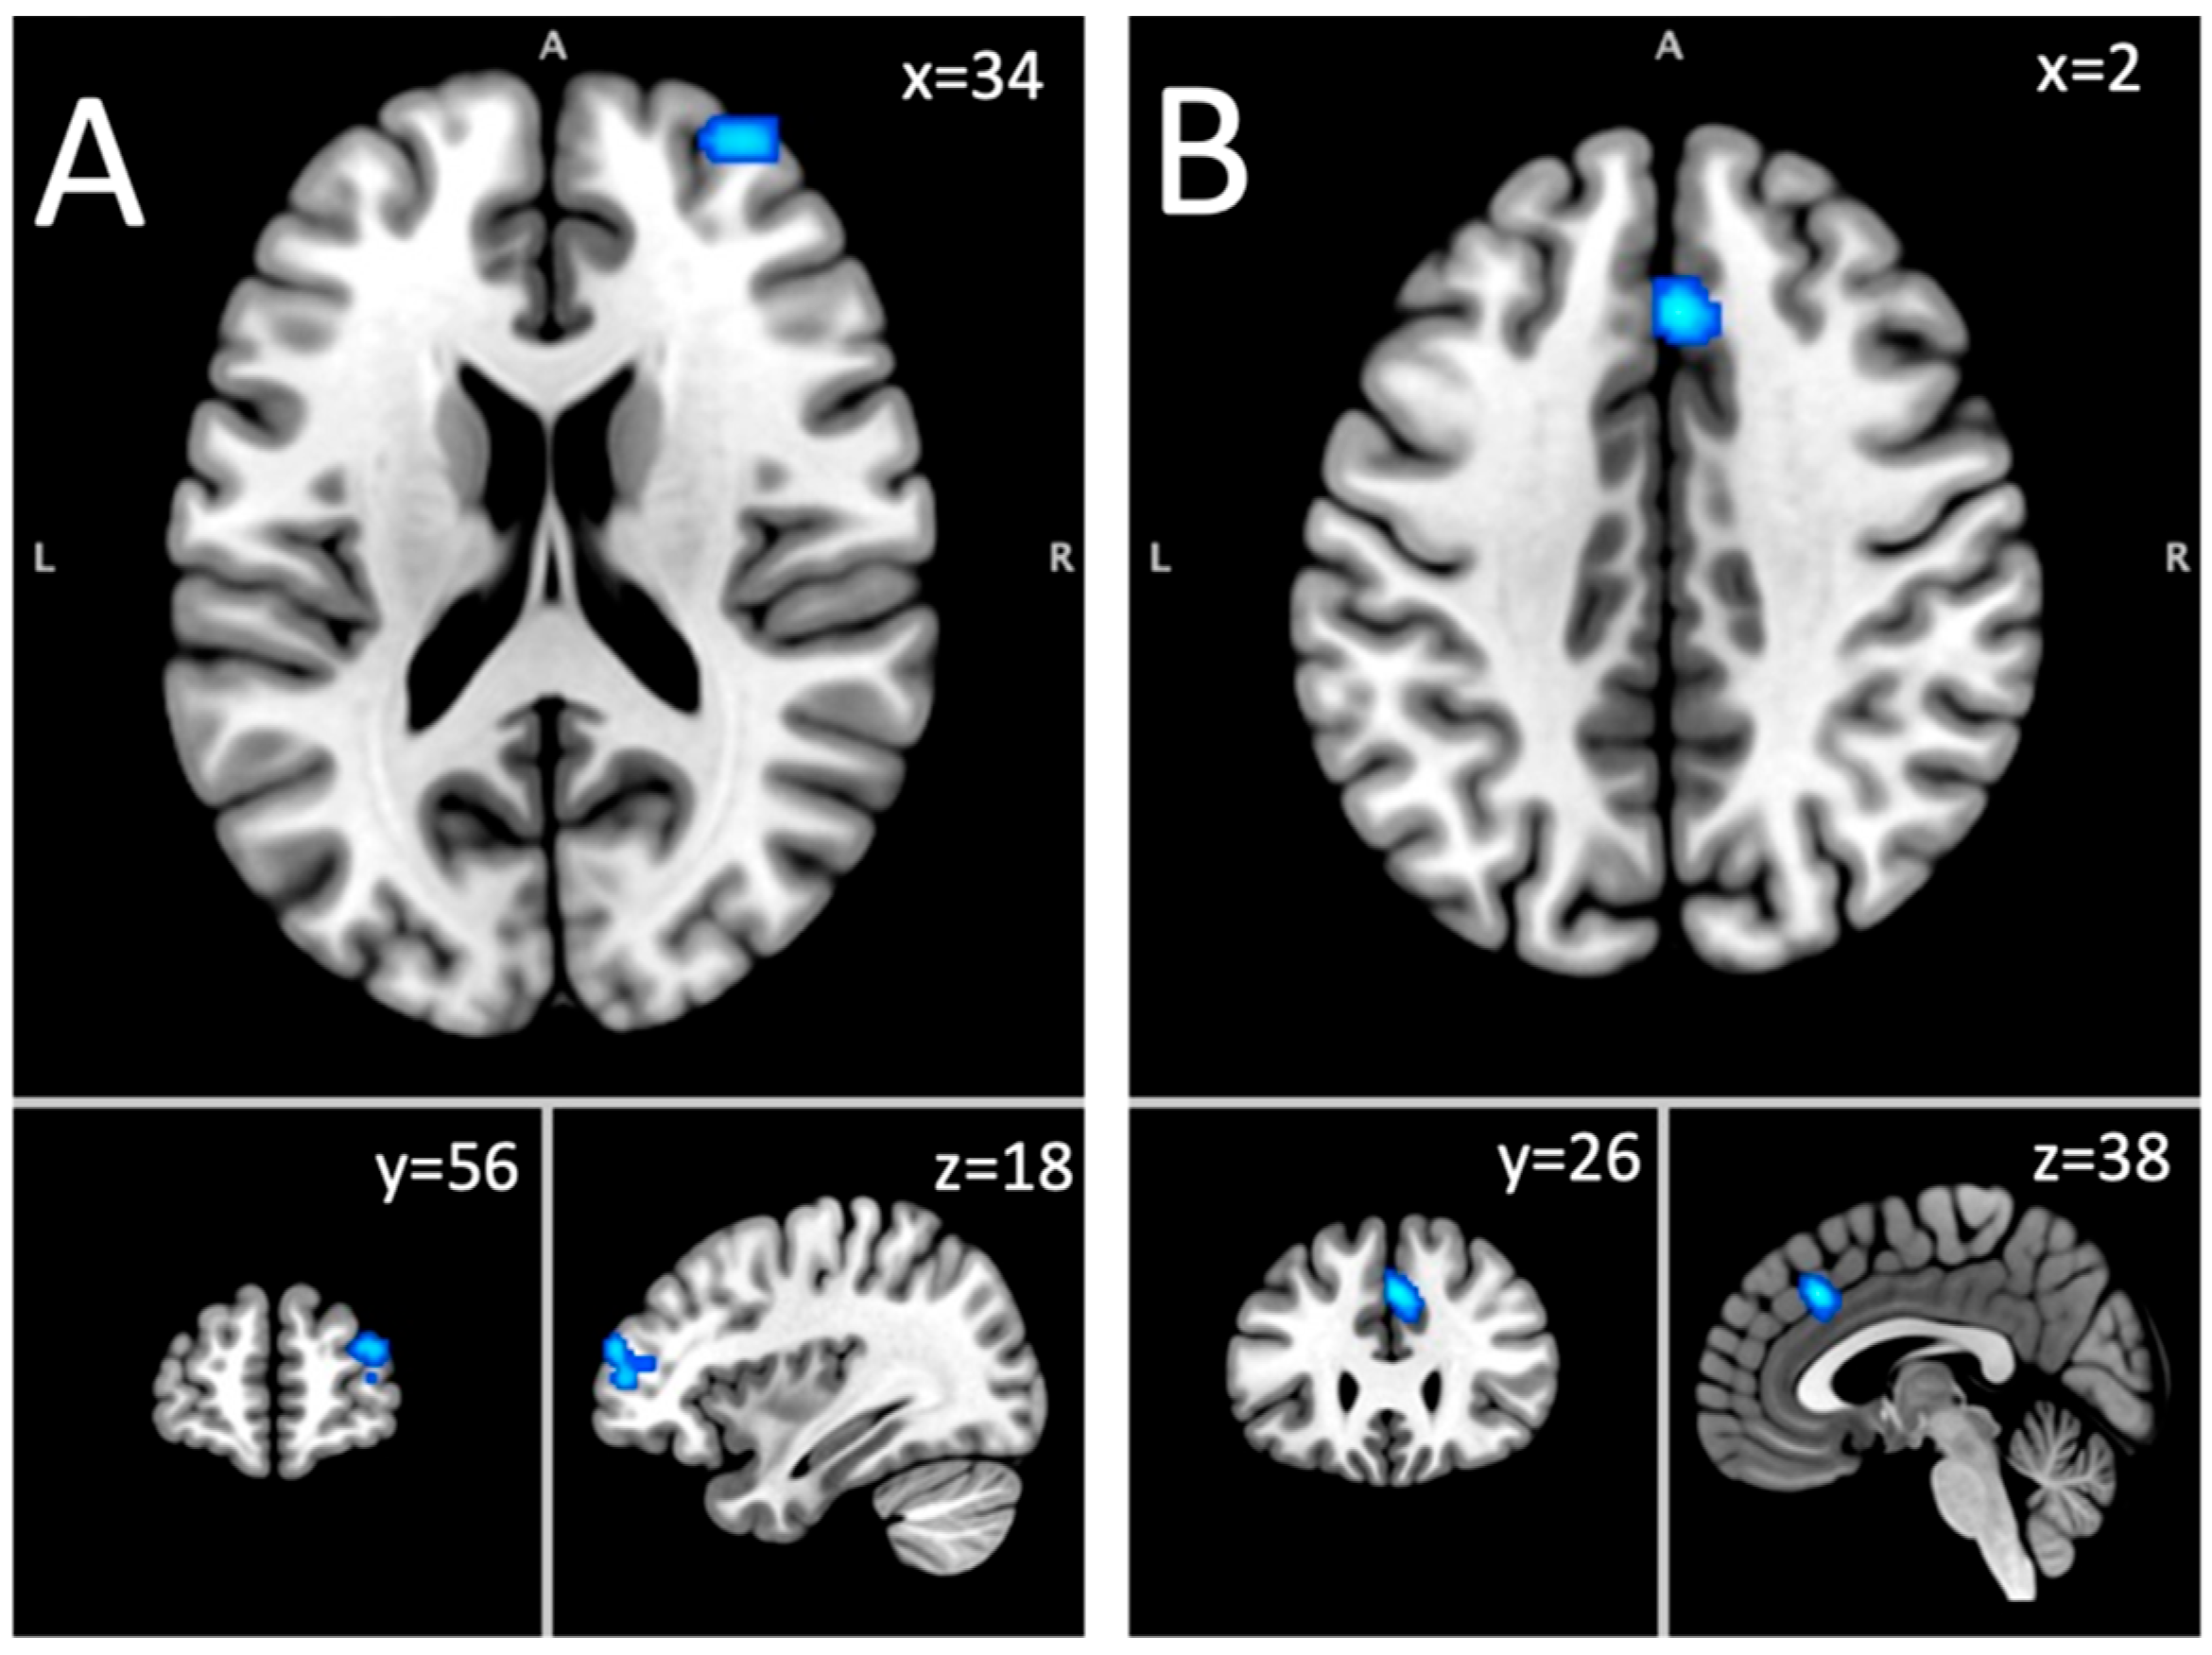

| Hypoactivation: long-term abstinent sample | |||||

| Superior frontal gyrus, middle frontal gyrus | R | 856 | 0.0147 | 3.85 | 34, 56, 18 |

| Cingulate gyrus, medial frontal gyrus | R & L | 800 | 0.017 | 4.26 | 2, 26, 38 |